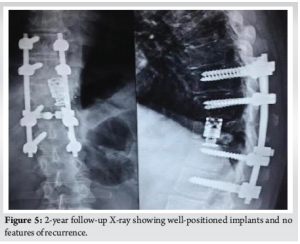

At 4-year follow-up, clinically he has excellent functional outcome and is free of recurrence (Fig. 5 and 6).

ABCs are a rare, benign locally aggressive type of lesion that usually appears in the early to mid-20s. They make up around 1% of primary bone tumors and 15% of primary spine tumors. Among the spine lumbar involvement is the most common, followed by the thoracic spine and cervical spine [1,2]. Here we report a case of thoracic spine ABC in an elderly patient. ABC arises from posterior elements of a vertebra and later involves the pedicles and vertebral body. Later on, there can be an intraspinal extension, which can cause neurological deficits [2]. Patients with an ABC often present with pain in the affected area along with neurological deficits. Paresthesia, paresis, and abnormal gait are common neurological manifestations when the spine is involved [1,2]. We e present a case of an elderly male patient with left-sided flank pain and abdominal pain and no other significant neurological symptoms. Computed tomography imaging typically shows an expansile, lytic lesion with a thin cortex and septae. MRI shows contrast enhancement with edema and fluid-fluid levels [9]. In this case, X-ray evaluation showed a pathological fracture of T 11 thoracic spine, and MRI showed expansile lytic multiloculated peripherally enhancing ill-defined lesion with a wide zone of transition replacing the entire normal marrow of the T11 vertebral body. The lesion showed a multiloculated bubbly appearance with fluid-layered locules. The differential diagnosis of lytic and expansive bone lesions includes solitary bone cyst, ABC, giant cell tumor, enchondroma, telangiectatic osteosarcoma, metastases, and plasmacytoma [2]. Treatment options for ABC are SAE, direct intralesional injection of sclerosants, intralesional excision (curettage), en-bloc excision and reconstruction, and/or radiotherapy [4,5]. We treated it with a 2-stage surgical procedure with posterior decompression, posterior stabilization, and biopsy in the first stage. HPE report was consistent with ABC. In the second stage T11 corpectomy, tumor excision and reconstruction with an expandable cage were done. Complete excision was achieved through the en bloc technique, However, this is a difficult procedure and has only been reported in rare cases[10]. The most common outcome of surgery is complete, piecemeal intralesional resection of ABC. The entire ABC must be removed, including all cyst walls and any abnormal tissues. In some cases, aggressive curettage may be used with high-speed drills to cut back into healthy bone. If the lesions are large and extensive, the most likely outcome is complete resection, which will likely result in iatrogenic instability and may necessitate instrumented fusion [2,8,9]. In this case, the postoperative period was uneventful. At 2 years follow up he demonstrated excellent functional outcome and showed no evidence of recurrence.